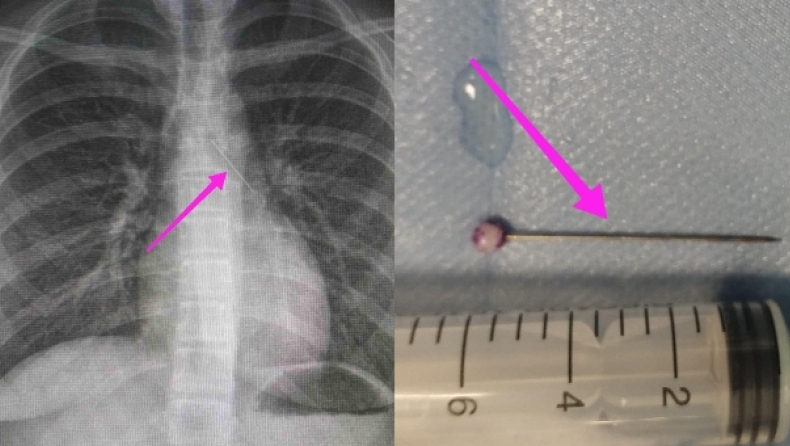

Οι γιατροί προχώρησαν σε απεικονιστική διερεύνηση του περιστατικού υποβάλλοντας την ασθενή σε ακτινογραφία και αξονική τομογραφία θώρακος, όπου διαπιστώθηκε η ύπαρξη του αιχμηρού μεταλλικού ξένου σώματος στην αναπνευστική οδό και συγκεκριμένα στον αριστερό κύριο βρόγχο και όχι στην πεπτική οδό.

Η ύπαρξη του αιχμηρού μεταλλικού ξένου σώματος ήταν στην αναπνευστική οδό και συγκεκριμένα στον αριστερό κύριο βρόγχο κι όχι στην πεπτική οδό.

Κατά την βρογχοσκόπηση διαπιστώθηκε η μετακίνηση και ενσφήνωση του ξένου σώματος στον δεξιό κύριο βρόγχο και μετά από προσπάθειες ολοκληρώθηκε με επιτυχία η αφαίρεσή του. Η ασθενής ανένηψε πλήρως εντός της χειρουργικής αίθουσας και μεταφέρθηκε για παρακολούθηση και νοσηλεία στη Γ’ Παιδιατρική Κλινική.